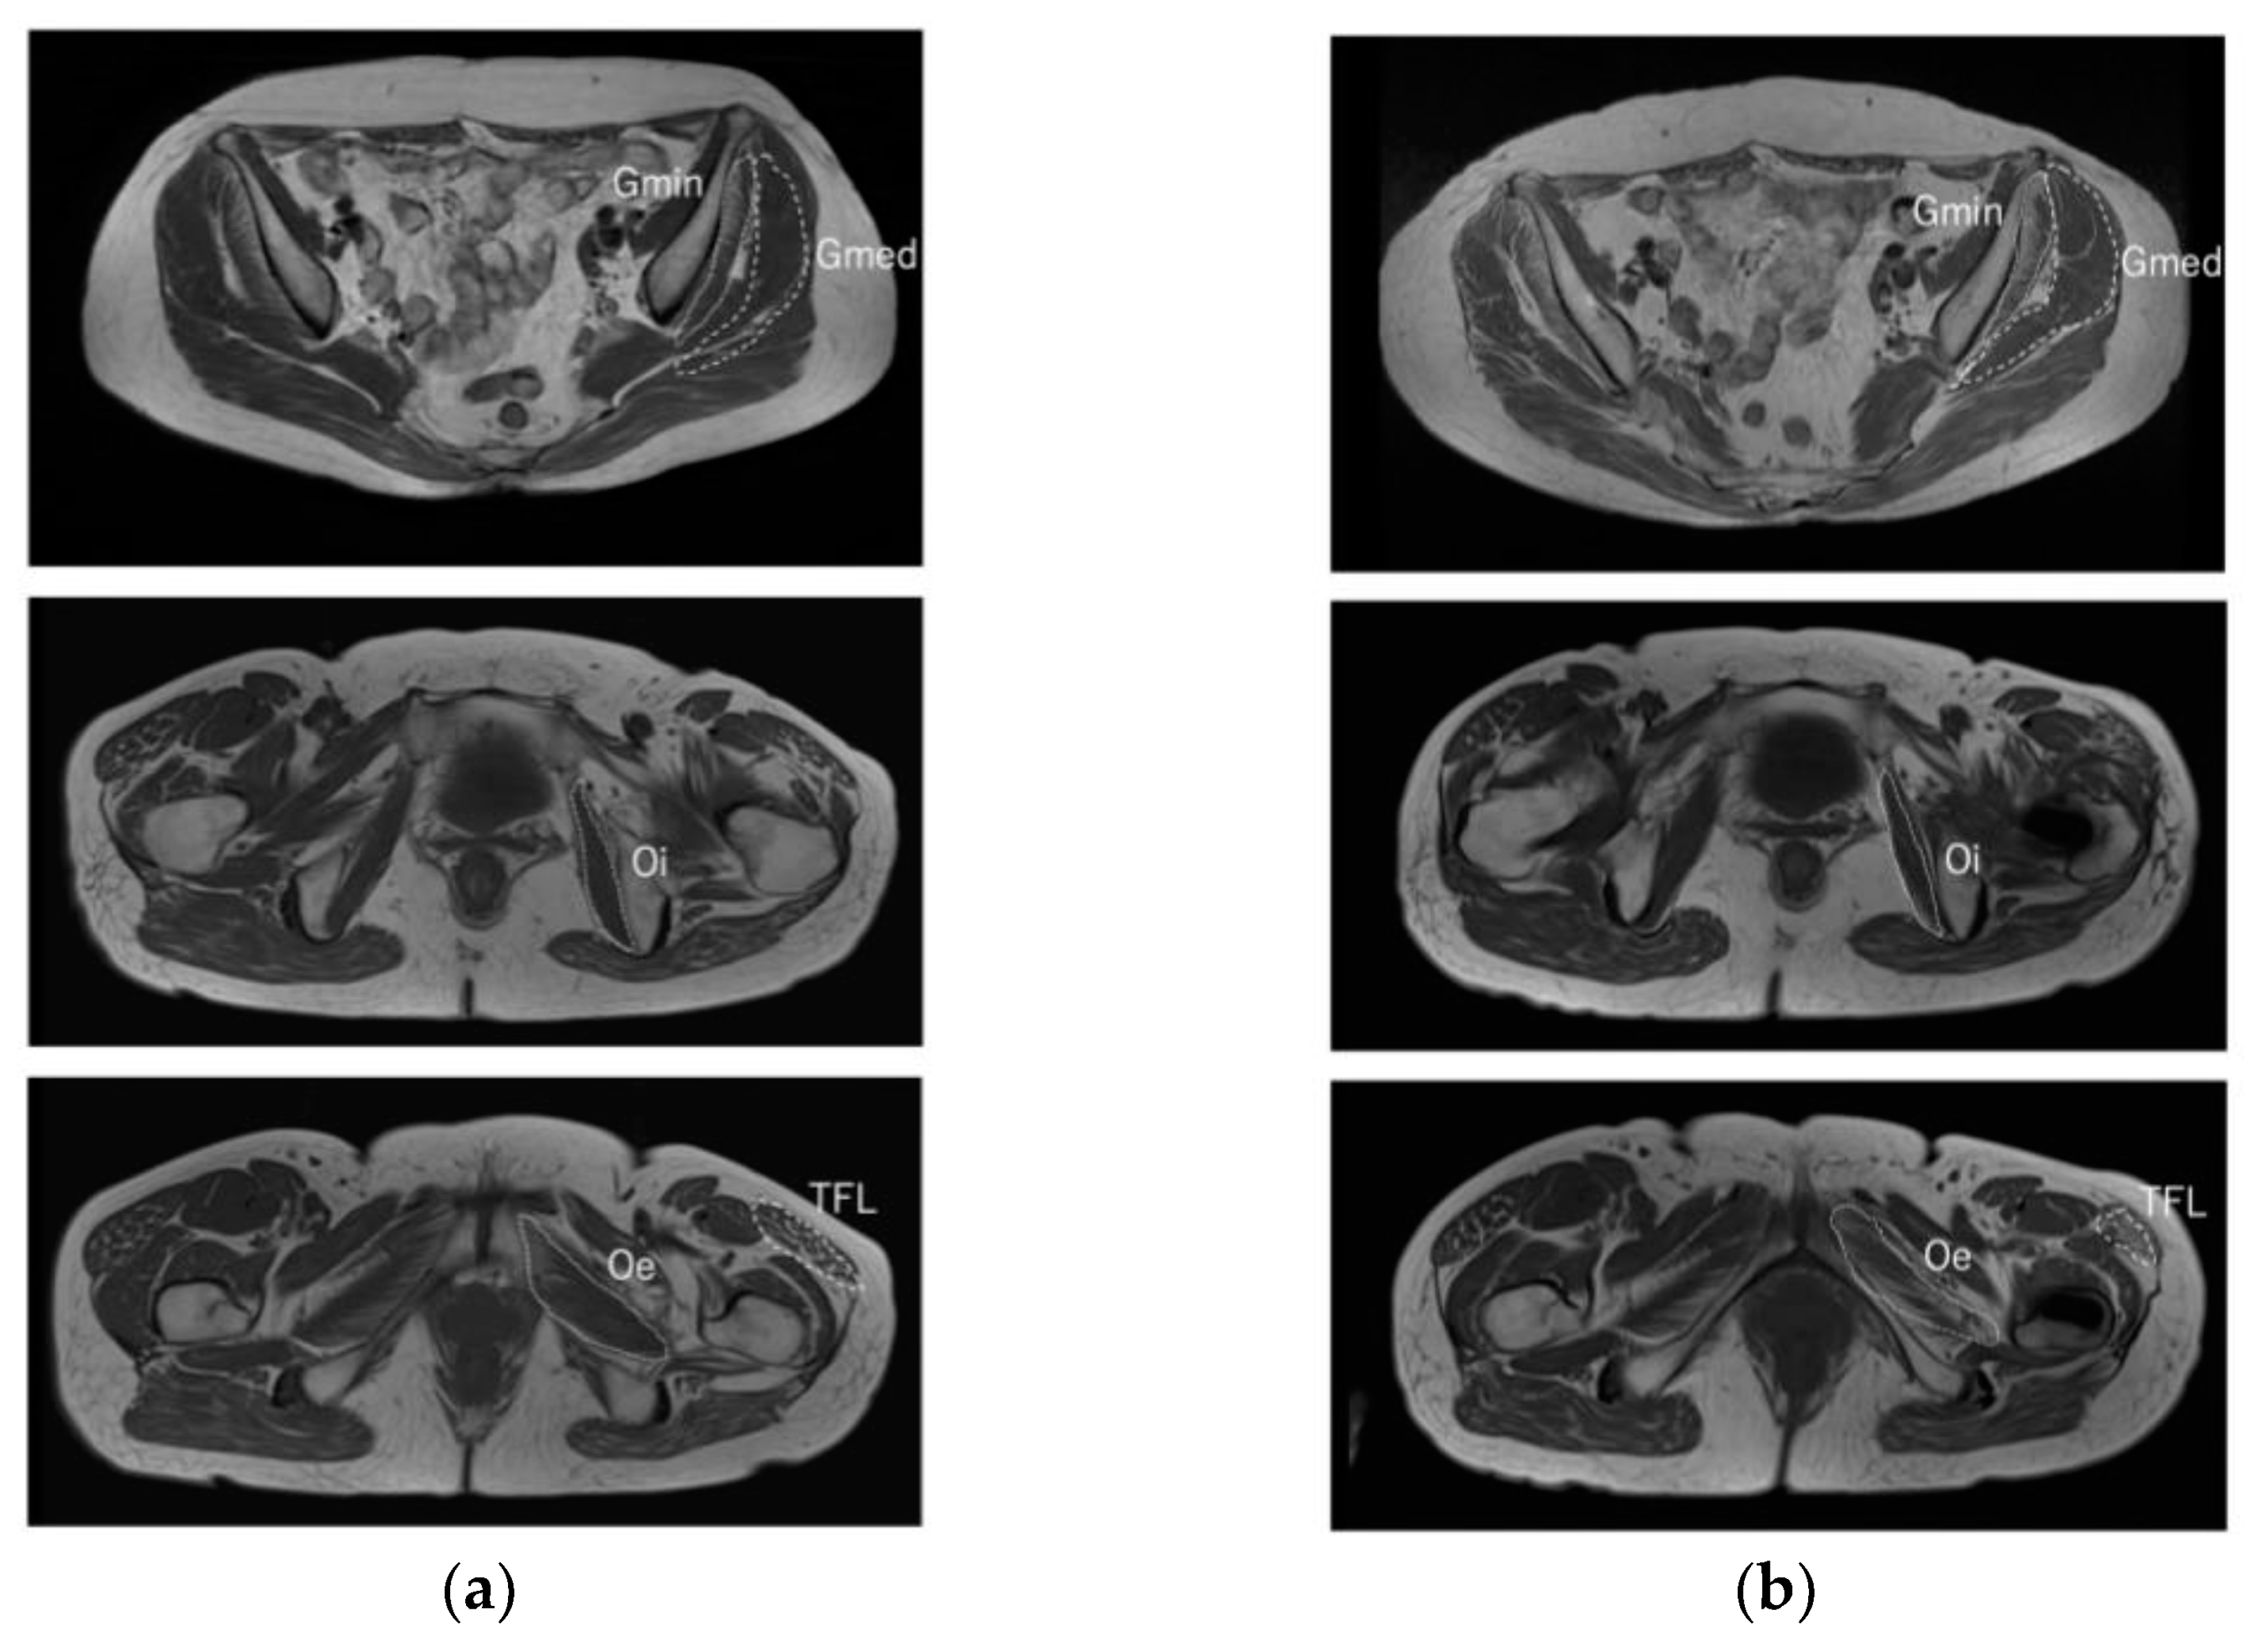

MRI Findings of Muscle Damage after Total Hip Arthroplasty Using the Complete Muscle Preserving Anterolateral Supine Approach